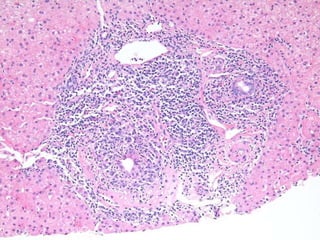

RFH case 3 38 yo, female.  Section from an explant specimen.  The patient was transplanted for end stage liver disease.

RFH 3  Dx: Liver: Explant - Primary sclerosing cholangitis.

RFH case 338 yo, female. Section from an explant specimen. The patient was transplanted for end stage liver disease.